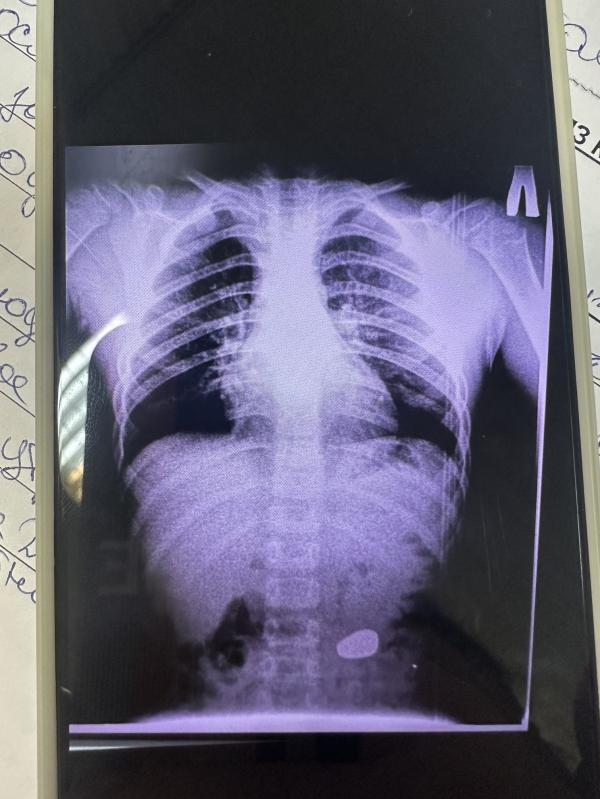

Вчера ребёнок проглотил магнит.

Ездили в больницу, сделали рентген, сказали ждать пока он сам выйдет. Вопрос- было ли так у кого? На какой день вышел инородный предмет?

Даем уже вторые сутки. Врач назначил касторовое масло и лактулозу.